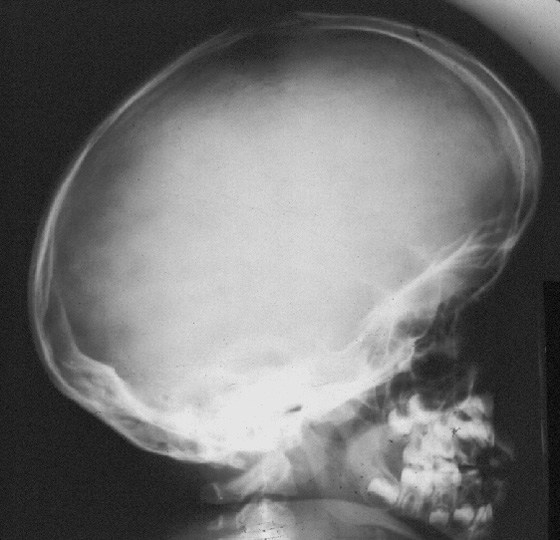

Macrocefalia y protuberancia frontal: se puede ver una cabeza inusualmente grande con una frente prominente.

| Créditos: Gamuts.isradiology.org |

Compresión medular a nivel del foramen magnum (que se muestra en la imagen a continuación) se puede encontrar en la primera infancia y en la niñez, causando apnea central del sueño, retraso en el desarrollo y señales de largo alcance (espasmos musculares y contracciones musculares involuntarias). Este problema tiende a resolverse con el crecimiento, ya que el tamaño del foramen magnum tiende a aumentar, en relación con el tamaño de la medula espinal. Aun así, la descompresión quirúrgica del foramen magnum puede ser necesaria en los bebés. Deben evitarse las actividades que conlleven un riesgo de lesión en la unión cráneo cervical.

También existe un pequeño riesgo de hidrocefalia, con presión venosa intracraneal elevada.

Foramen Magnum – donde la médula espinal se conecta con el cerebro. Créditos: Foramen magnum - Wikipedia. |